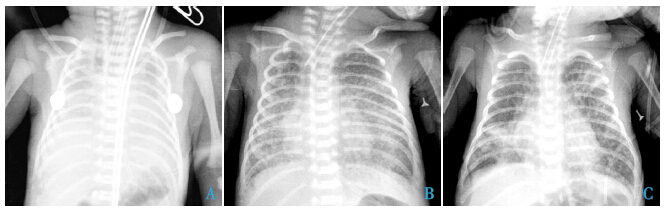

BPD 患儿胸部X 线检查主要表现为新生儿 RDS、经典型BPD Ⅲ期及Ⅳ期表现。图 1 示BPD 患儿1 d、18 d 及28 d 的胸部X 线表现。

图 1 胸部X 线表现 A:生后1 d,呈RDS Ⅳ级改变;B:生后18 d,呈线条状或斑片状阴影间伴充气的透亮小囊 腔改变;C:生后28 d,表现为双肺野透亮区扩大呈囊泡状,伴两肺结构紊乱、散在条状或斑片影 |